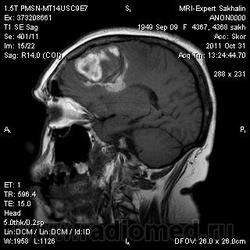

Объем головного мозга.МРТ головного мозга.

Пациентку беспокоят головные боли, нижний парапарез.

менигиома с кровоизлиянием

Картина не такая простая на самом деле, не типичная для менингиом. Менингиома, возможно, атипическая менинготелиоматозная. Учитывая такую "пеструю" структуру, перитуморальную реакцию можно сделать вывод вообще об анаплазии...

Но все же признаки менингиомы имеет-прилежание к ТМО,сигнальные характеристики, "дуральный хвост"при контрастировании))))

8й пост. Менингиома с признаками анаплазии.

Сегодня один мой коллега высказал мнение, что образование интрааксиальное и предположил глиому. Как вам такая точка зрения, коллеги?

Легко может быть,поэтому и говорю, что не все так просто и все эти симптомы весьма условны и не типичны для менингиомы. Так можно и до гемaнгиoперицитомы договориться, но это будут лишь предположения.